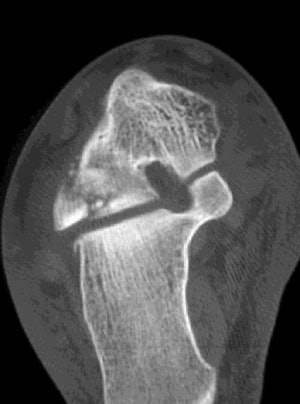

![]() |

| Axial CT image demonstrates comminuted fracture of the lateral process of the thalus that extends into the posterior talocalcaneal joint. |